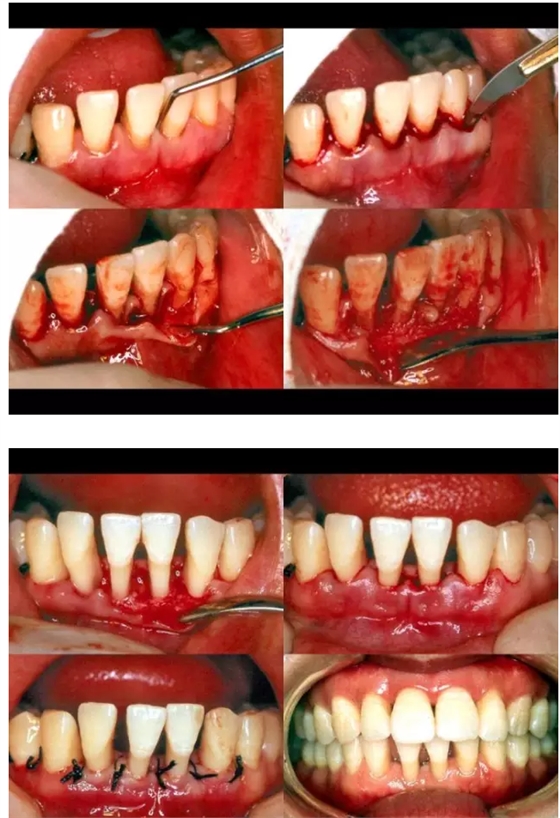

50.png

51.png

52.png

53.png